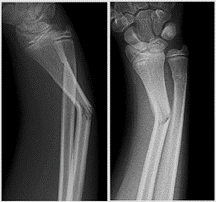

Greenstick and buckle fractures

- Buckle fractures occur when the thin cortex buckles under the force of a fall, but no displacement occurs, and continuity of the cortex is not disrupted.

- Greenstick fractures occur when a force breaks one cortex, but the other remains intact and acts as a hinge.

- All diaphyseal fractures, including greenstick, should be reduced and immobilised until union is achieved. Immobilisation can be in the form of a plaster cast (tibia fractures), a backslab (fractures around the elbow) or a sling (clavicle and proximal humerus fractures).